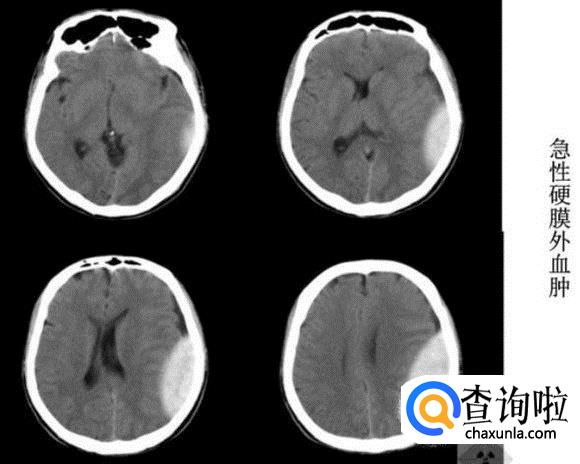

硬膜外出血

分为急性期、亚急性期、慢性期。可见颅骨内板下梭形或双凸形高密度,根据血肿量不同,可有不同程度的占位效应,如脑沟消失、脑室受压变形、中线结构移位等。随着时间延长,其密度可由高变等密度、变低密度。